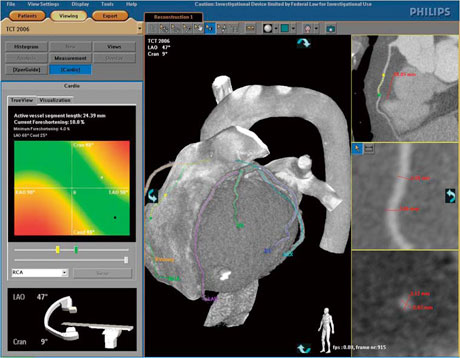

心臓CTの進歩は目覚ましく,現在では多くの施設で活用されている。心臓CTでは,高精細な3D画像が生成され,これらは複雑なPCI時に多用され始めている。フィリップスでは,心臓CTデータを利用し最適なアプローチアングルをシミュレートして,目的のワーキングアングルへのオートポジションを実現する“CT TrueView”を開発した。このアプリケーションソフトウェア上で術者は,選択病変部の最適なアングルを選択することができる。また,Optimal View Map機能により,臨床角度を装置側が自動計算し提示する(図3)。

図3 CT TrueView